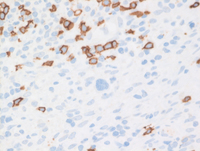

Low power H&E Image

Low power image demonstrates broad bands of compartmentalizing sclerosis noted as the pink areas with nodular structures containing an atypical lymphoid infiltrate.

High power at the periphery of the nodule demonstrates prominent sclerosis with mottled appearance to the nodules due to scattered large atypical cells with somewhat clear cytoplasm present in a background of small lymphocytes.